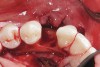

Figure 4  Vertical ridge defect in site No. 22.

Figure 4

Figure 5  Horizontal ridge defect in site No. 22.

Figure 5

The patient had no medical concerns and had a history of an implant placement in December 2002 when she was 25 years old. In February 2005, she presented with a mobile implant and an associated advanced peri-implantitis. Radiographic review at the initial examination demonstrated significant destruction of the dentoalveolar ridge around the implant as well as around the adjacent natural dentition. Emergency-based treatment involved surgical implant removal only and debridement of the infection (Figure 4 and Figure 5). Following uneventful healing, an advanced ridge defect was apparent at the edentulous site and moderate and advanced attachment loss noted at No. 22D and No. 21M, respectively (Figure 6 and Figure 7). This case demonstrates bone loss of two separate origins: lack of bone because of tooth agenesis and destruction of bone from inflammatory peri-implantitis.